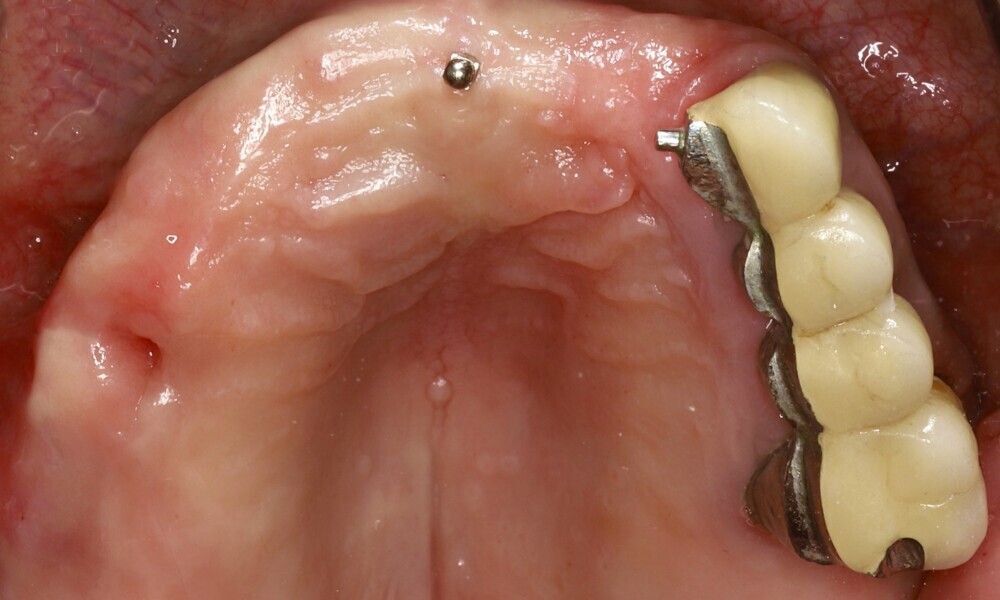

Extra-oral examination showed no significant abnormalities. The patient presented with a medium smile line (Figs. 1–3). The intra-oral examination revealed a fixed bridge spanning teeth #23–26 to which the removable metal partial denture attached (Fig. 4). Teeth #22–17 had been extracted a long time before, and the ridge in this region had healed. No plaque or inflammation was observed. The teeth exhibited mild to moderate attachment loss, but no endodontic or periodontic lesions or root fractures were observed (Figs. 5–8). Analysis of the panoramic radiograph indicated sufficient vertical and horizontal bone availability and adequate bone quality; therefore, there was no need for guided bone regeneration (Fig. 9). According to the International Team for Implantology’s SAC classification, the case was categorised as advanced to complex.

The fit of the previously sterilised provisional guide and surgical guide was then verified (Figs. 21 & 22). The surgical guide was positioned, aligning it with the arch and extraction sockets. Subsequently, the holes for the anchor pins were drilled and the pins inserted (Figs. 23 & 24). The surgery was initiated using a mucosa punch at 15 rpm through the sleeves of the surgical guide. This method allowed for blade-free incision with minimal trauma (Figs. 25 & 26). After removing the mucosal punch, the surgical guide was reinserted to begin the placement of the implants (Fig. 27). The surgical protocol, provided alongside the surgical guide, recommended the sequence of instruments required to prepare each implant site. The osteotomy sites were prepared following the manufacturer’s recommended drilling protocol using a copious amount of saline irrigation, and the implants placed as follows and parallelism checked (Figs. 28–31):